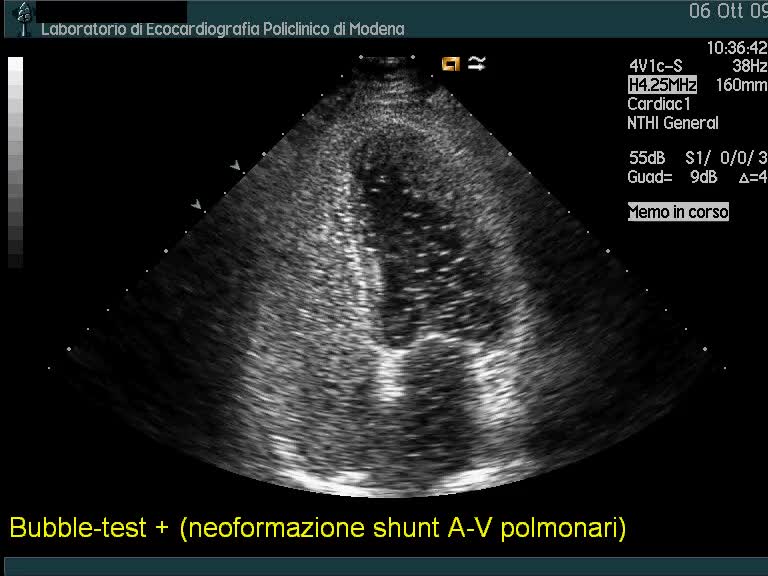

Neoformazione di shunt artero-venosi polmonari

Autore:

Andrea Barbieri